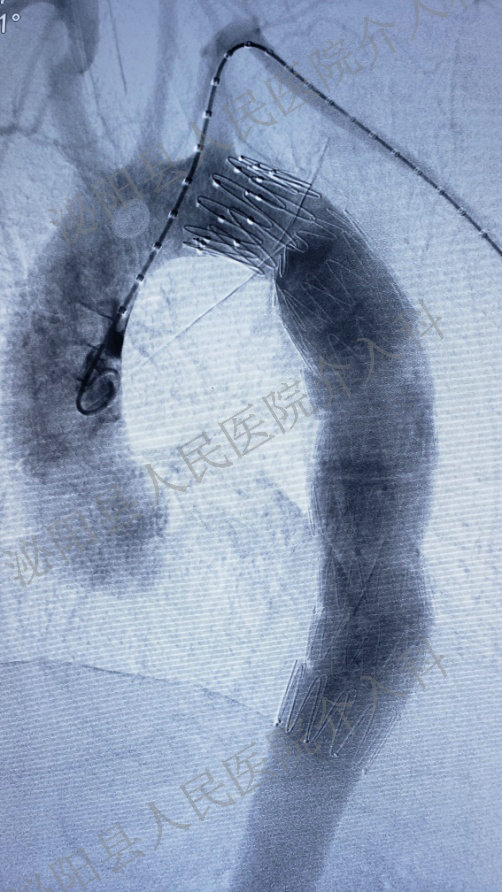

支架植入术后血管重塑

腹主动脉瘤病情凶猛,每耽搁一秒就有随时破裂的风险,使患者失去生命。在介入科代主任的带领下,经多学科专家会诊,反复讨论、评估,并与家属充分沟通后,决定采用覆膜支架腔内隔绝术进行治疗。覆膜支架腔内隔绝术,隔绝动脉瘤腔,重塑血管,解除动脉瘤璧受到的血流冲击并且保持腹主动脉管腔通畅。该疗法从根本上防止腹主动脉破裂,避免发生致死性大出血。